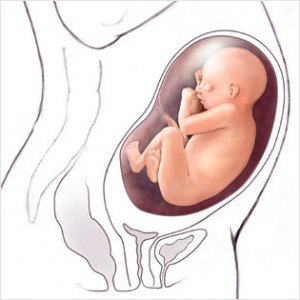

Hamileliğin (Gebeliğin) 35. Haftası Resim ve Video;

Bebeğin Boyutu: 43.7 cm, 1.9 kg

Çocuğun gelişimi: akciğerler alveollerin genişlenmesini sağlayacak ve doğduktan sonra bebeğinizin nefes alması için önemli olan surfaktan (Surfaktan maddeler en basit tanımı ile bir sıvının yüzey gerilimini azaltan maddelerdir) üretiyor.

Böbrekler tamamen gelişmiştir.

Bu haftadan itibaren artık bebek rahim içerisinde oldukça fazla yer kaplar ve bu yüzden ona hareket edecek fazla alan kalmaz. Eğer bebeğinizin hareketlerinde azalma his ederseniz endişe etmeyin, hareketlerin azalması bu yüzdendir.